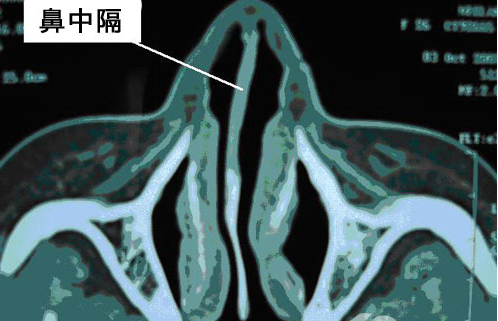

圖:鼻中隔偏曲CT

鼻中隔偏曲是指鼻中隔發生偏曲,一般偏向一側或兩側。常見的癥狀為鼻塞,由于鼻中隔會向一側或兩側偏曲,可導致單側鼻塞會雙側鼻塞。鼻中隔偏曲也可有可能出現局部有突起的現象,常導致鼻腔功能障礙,如鼻出血、頭痛、張口呼吸、睡眠打鼾等。